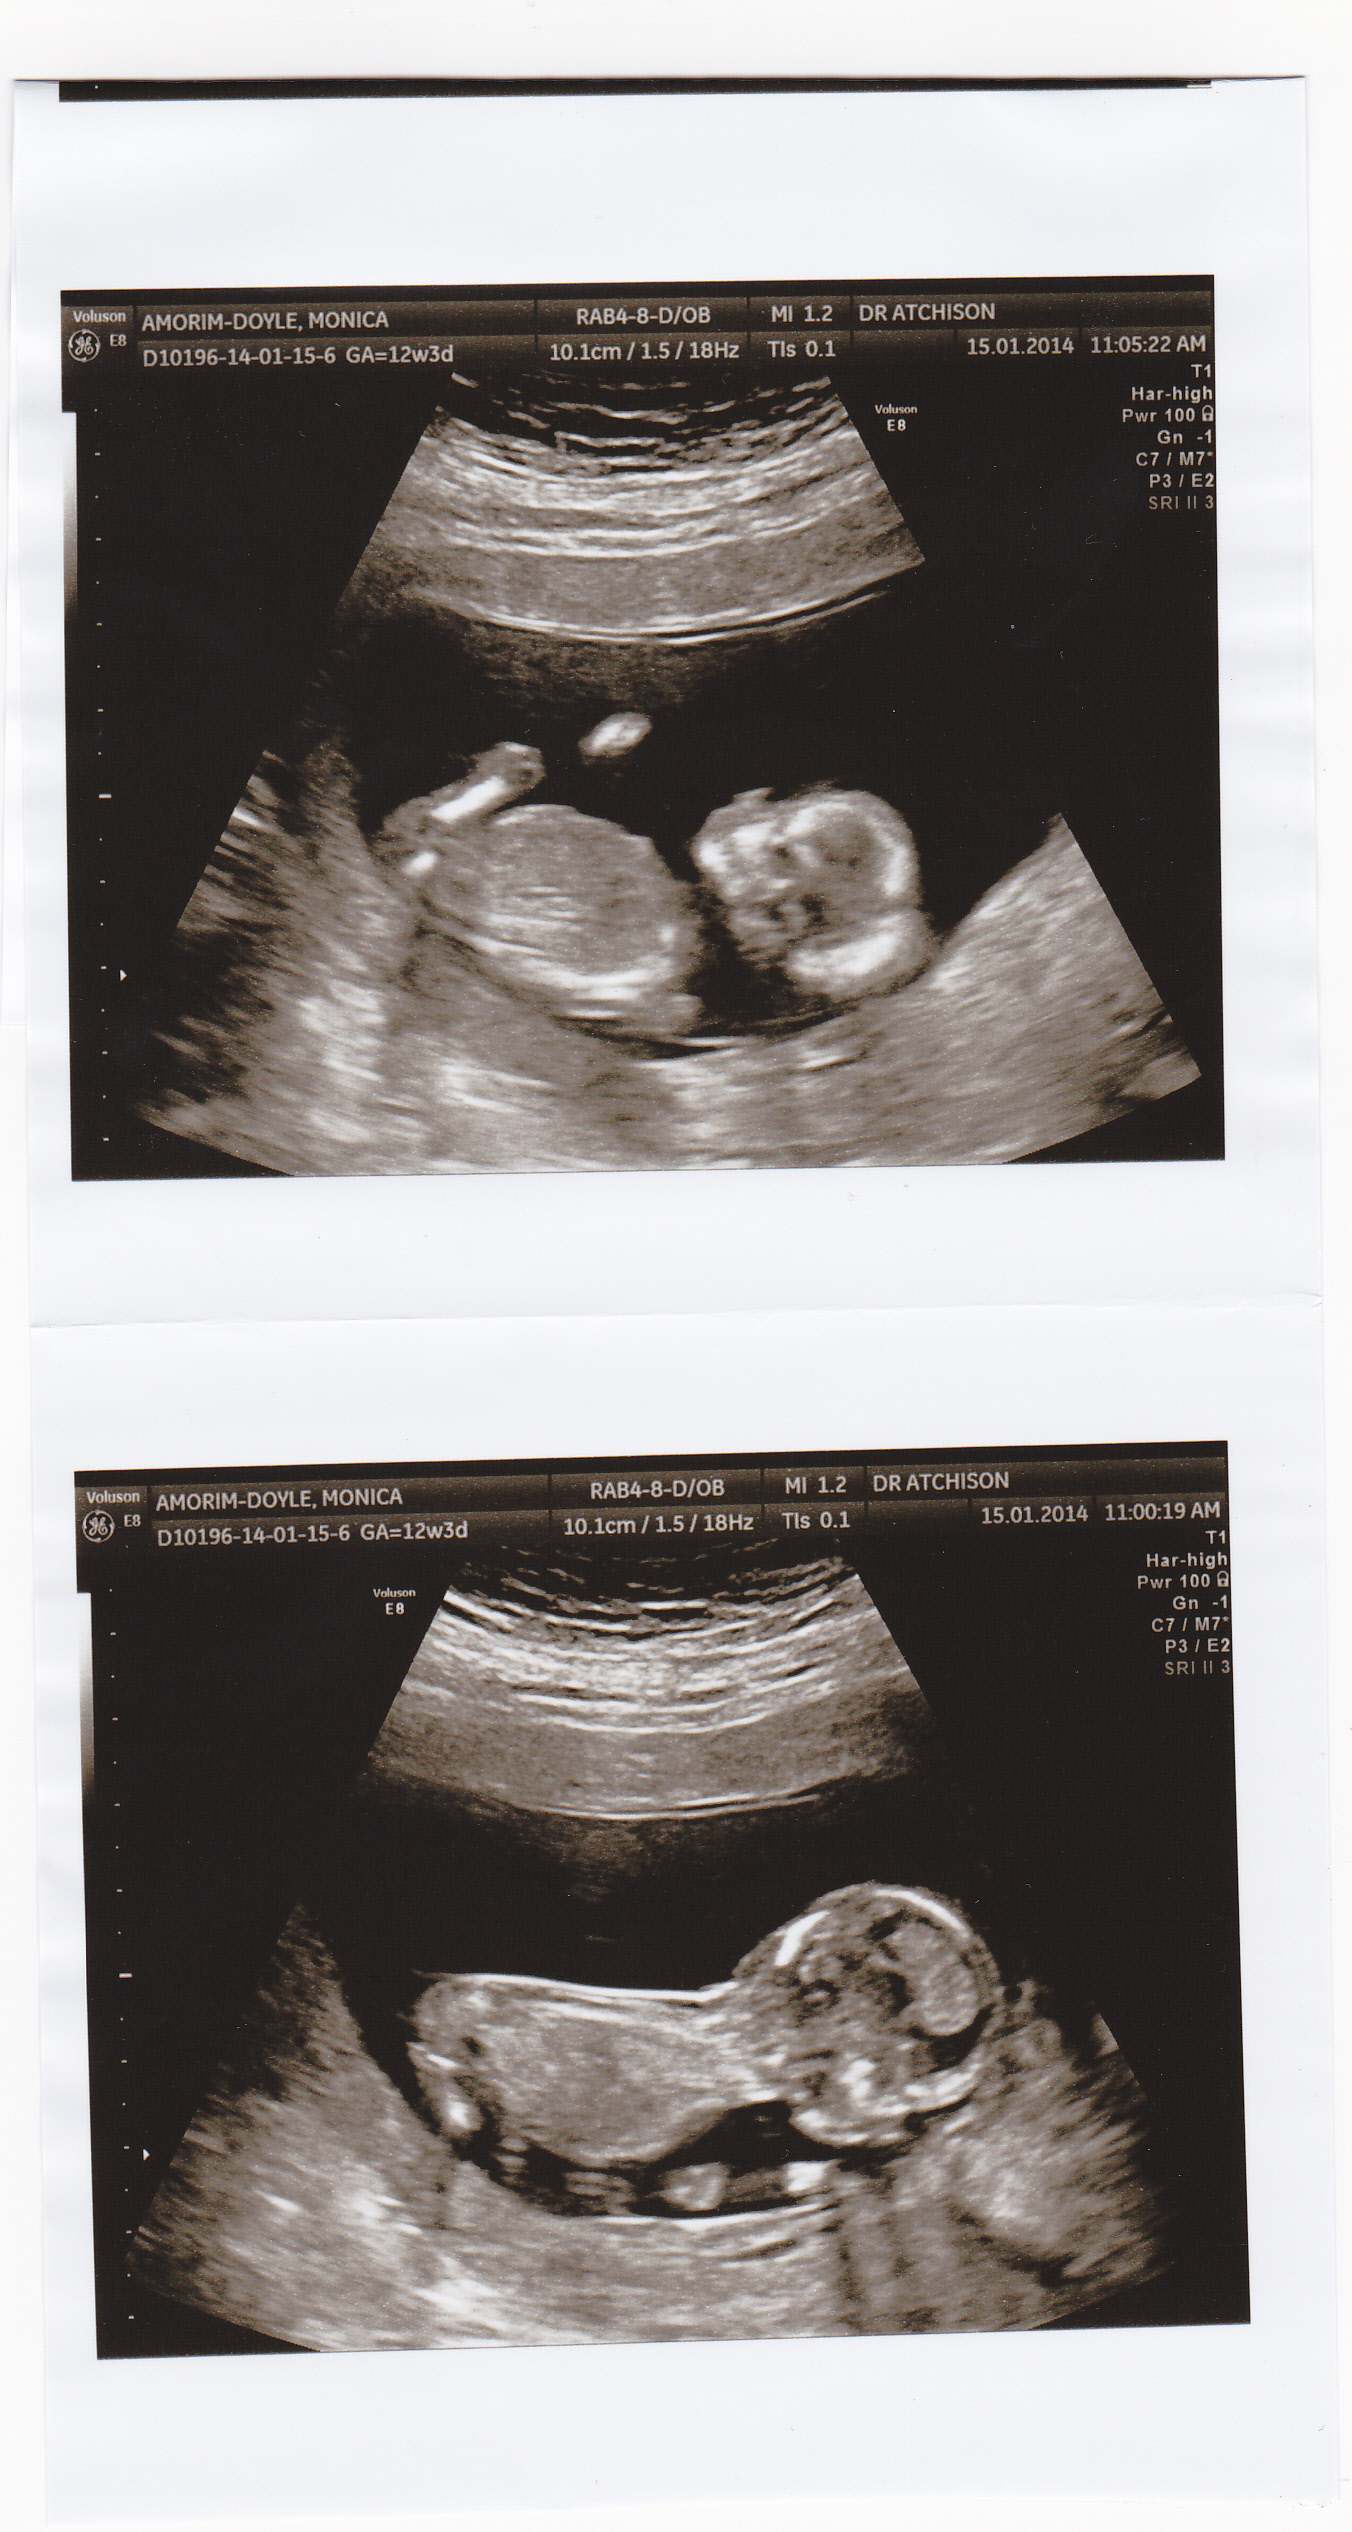

Hi. Can I lend your skull or nub skills ladies? My baby was doing push ups and on its tummy first so I couldn't really see a nub, I don't even think there is a nub there (if you see something, please let me know) so I am relying on skull theory to shed some light on baby's gender.

I will find out in 2 weeks and will update then.

Attachment 16341